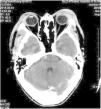

Kimura's disease (KD) was initially described by Kim and Szeto in 1937, and became better known after a systematic description provided by Kimura as a chronic inflammatory disease.1 Most cases reported occurred in Asian men between 20 and 30 years of age.2 Therapeutic modalities for KD include surgical excision, radiotherapy, and various immunomodulating agents, such as oral corticosteroids, cyclosporine, leflunomide, and mycophenolate mofetil.3 We report a case of KD with an excellent and sustained response to oral corticosteroid and intravenous methotrexate. A 51-year-old man presented with a history of fullness of the bilateral upper eyelids and a similar swelling in the bilateral parotid regions for seven years (Fig. 1); itching or pain symptoms. Physical examination revealed soft, pendular, non-tender mass lesions on both lateral upper eyelids, resulting in mechanical ptosis. The remainder of the ocular examination was within normal limits. His past medical history was unremarkable. Complete rheumatologic and immunologic workup was performed. Complete blood count showed the total number of white blood cells was 8.3×109/L, neutrophils 4.35×109/L (accounting for 52.4%), lymphocytes 2.50×109/L (accounting for 30.1%), and eosinophils 1.01×109/L (accounting for 12.2%). Serum IgE was 205IU/mL (normal, <100). Remaining laboratory results were normal. Computed tomography scan revealed soft-tissue lesions involving both the upper eyelid and parotid regions. A post-contrast study showed intense homogeneous enhancement on delayed scans (Fig. 2). Histopathology of the lesion excised from the left upper eyelid showed lymphoid tissue hyperplasia, with lymphoid nodules containing germinal centers that were scattered in the dermis and subcutaneous tissue, with scattered eosinophilic infiltration (Fig. 3). Based on the clinical manifestations and histopathological features, KD was then diagnosed. The therapeutic regimen comprised a tapering dose of oral prednisone (initial dose 40mg/d) and intravenous methotrexate at 15mg/week for two months. The patient had complete resolution after treatment and there was no recurrence in the next two years of follow-up. KD is a chronic inflammatory disease that manifests as a triad of subcutaneous nodules in the head and neck region, peripheral blood eosinophilia, and elevated serum IgE.3 It may also involve extracutaneous sites, such as regional lymph nodes, major salivary glands, and the kidneys. However, renal involvement is not uncommon and most frequently results in nephritic syndrome.4 The patient presented all the three typical elements to fulfill the diagnostic criteria and both sides of salivary glands had been involved. Thus, KD was the first diagnosis considered. This disease must be distinguished from angiolymphoid hyperplasia with eosinophilia (ALHE) because of several overlapping clinical and histologic features. KD occurs mainly in young men of Asian descent with one or multiple asymptomatic masses involving the subcutaneous tissue and salivary glands. It is often accompanied by regional lymph node involvement, peripheral blood eosinophilia, and elevated IgE. In contrast, ALHE occurs predominantly in middle-aged women, presenting with multiple small papules or erythematous nodules associated with itching.1 In the histopathologic features, KD displays the presence of numerous lymphoid follicles and the absence of irregular, dilated blood vessels,2 just like what was observed in this case. The pathogenesis of KD remains unknown, but allergy, atopy, autoimmunity, and parasite infestation are considered possible risk factors.3 Previous studies have found increased levels of interleukin-4, interleukin-5, and interleukin-13 in the peripheral blood of affected individuals, suggesting a role for type 2 T-helper cytokines.5 Therapeutic methods reported in the literature are heterogeneous, but surgical excision and oral corticosteroids represent the most frequently used strategies.3 To avoid recurrence in the course of tapering steroids, various immunomodulating agents should be added in the treatment plan. Leflunomide and mycophenolate mofetil have shown promise effective in some reported cases.3 But the two drugs are still expensive, so we chose methotrexate as the combined drug, which exhibits immunomodulatory effects in a similar fashion by inhibiting de novo purine synthesis via inosine monophosphate dehydrogenase. Although recurrence is very common, it did not occurred in the present patient within the next two years of follow-up. The author feels that methotrexate may be a promising therapy for KD.